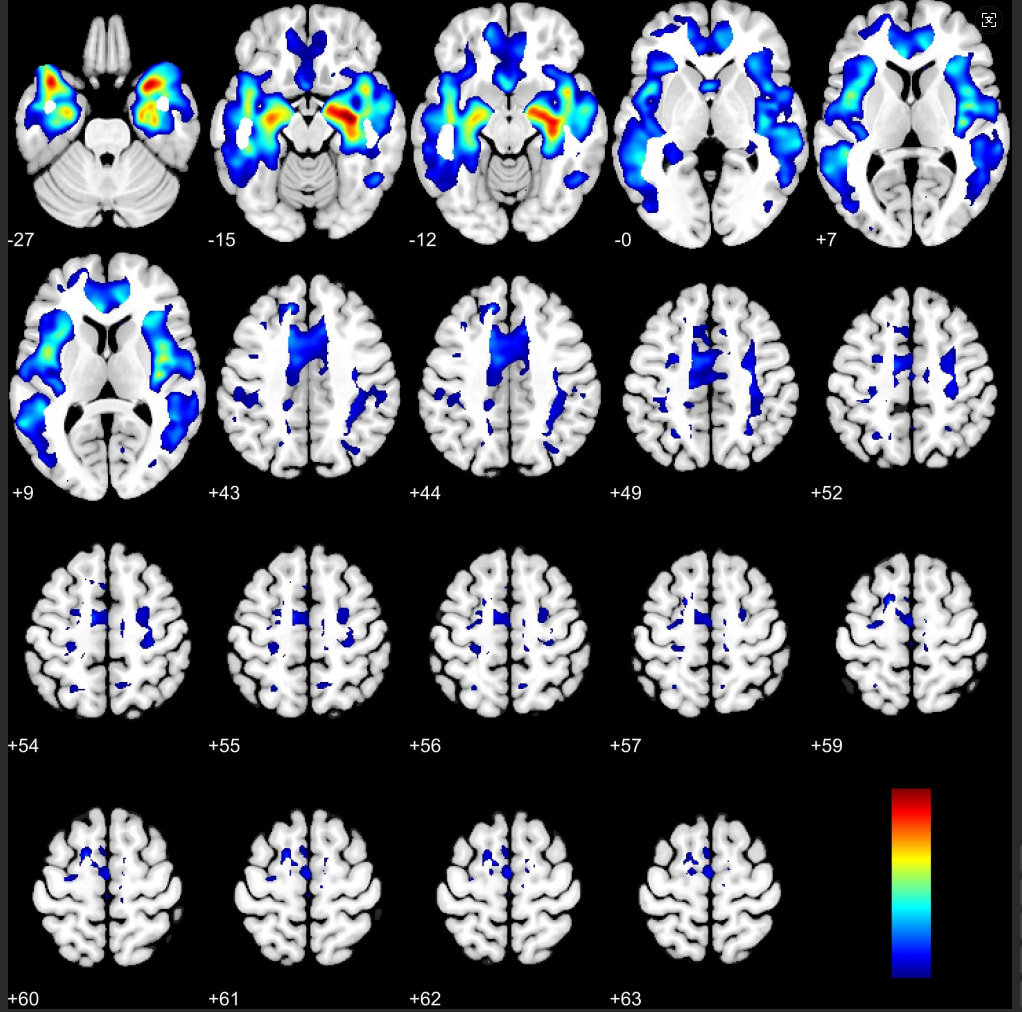

结果:

谢谢老师指正,这是截图的时候的错误,在我的实际分析中,选的是NO,在统计模块处不知道是否有其它的错误?还望老师指正。结果的图片是上述这样的。然后我用常用的segment和配对t检验做了结果进行了比对,差异脑区也是非常明显,并且体素比较大,结果如下图,和纵向分割的比较结果有所区别,麻烦老师看一下是否有误。

然后我将配对t检验的结果在cat12的result模块用transf.spm.maps中的T-volume-map模块进行FWE校正,结果如下: